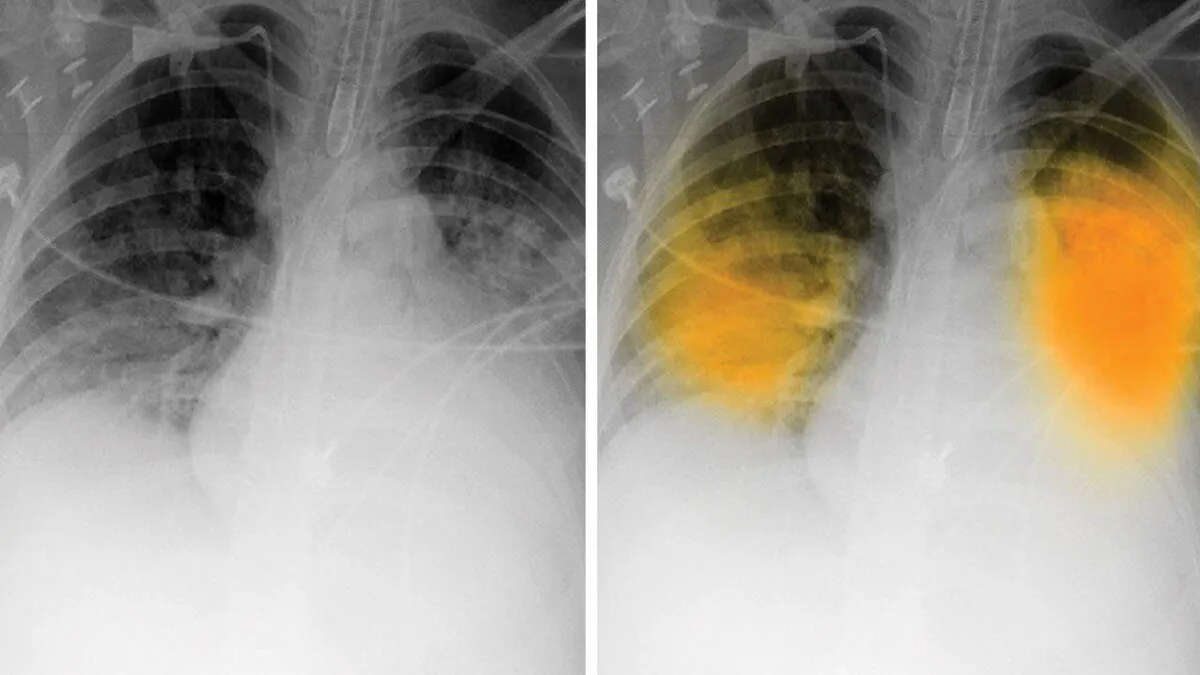

نتایج یک پژوهش جدید نشان می‌دهد که اگرچه ابزارهای هوش مصنوعی قادر هستند به رادیولوژیست‌ها در تشخیص و تفسیر تصاویر کمک کنند؛ اما نمی‌توان به آن‌ها برای شناسایی بیماری‌های رایج ریوی در عکس‌برداری با اشعه ایکس قفسه سینه اعتماد کرد.

در این مطالعه از تصاویر اشعه ایکس برای بررسی سه یافته رایج استفاده شد که شامل این موارد هستند: بیماری حفره‌های هوا در ریه که یک الگوی اشعه ایکس قفسه سینه بوده و معمولاً پس از ابتلا به ذات‌الریه یا آدم ریه ظاهر می‌شود، پنوموتوراکس یا فروپاشی ریه؛ و پلورال افیوژن، تجمع آب در اطراف ریه‌ها.

در این پژوهش مشخص شد دقت تشخیص ابزار‌های هوش مصنوعی از ۷۲ تا ۹۱ درصد برای بیماری حفره‌های هوا، ۶۳ تا ۹۰ درصد برای پنوموتوراکس و ۶۲ تا ۹۵ درصد برای پلورال افیوژن متغیر بودند در شرایطی که رادیولوژیست‌ها در شناسایی دقیق وجود و عدم وجود سه بیماری رایج ریوی از هوش مصنوعی به‌مراتب بهتر عمل کردند.

به گزارش آنا، پلزنر در این رابطه گفت: ابزار‌های هوش مصنوعی حساسیت متوسط تا بالا را در مقایسه با رادیولوژیست‌ها برای تشخیص بیماری فضای هوایی، پنوموتوراکس و پلورال افیوژن در اشعه ایکس قفسه سینه نشان دادند. بااین‌حال، آن‌ها نتایج مثبت کاذب بیشتری نسبت به رادیولوژیست‌ها داشته و در حقیقت دچار تشخیص اشتباه می‌شدند.

شواهد این مطالعه نشان می‌دهد هوش مصنوعی بدترین عملکرد را در شناسایی بیماری حفره‌های هوایی با ارزش‌های پیش‌بینی مثبت بین ۴۰ تا ۵۰ درصد داشت.